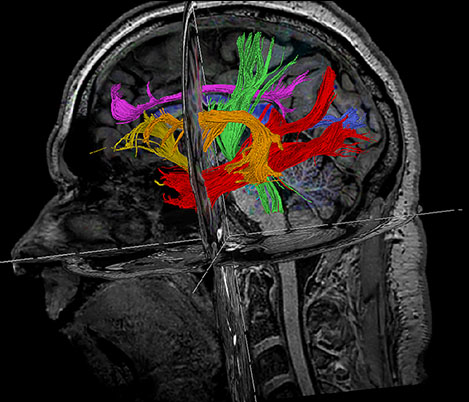

APT** and REACT**: The next steps towards non-invasive imaging strategies for pediatric MRI

Jeffrey H. Miller, MD

Vice Chair of Radiology for Research and Academic Affairs, Phoenix Children’s Hospital, Phoenix, AZ, USA